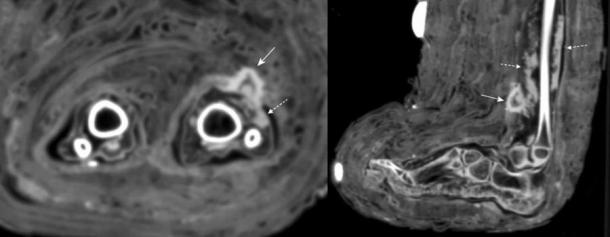

CT scans of soft tissue infection in the lower leg of the child mummy. The scan reveals a mass consistent with dried pus (indicated with dotted arrows) below the bandage. (Panzer et. al / International Journal of Paleopathology)

In total, three out of the 21 children showed signs of skin lesions and infection. But only the one girl, who was no more than four when she died, had a bandage still attached to the skin over her wound. Writing in the International Journal of Paleopathology, the researchers referred to their study as “the first to describe radiologically visualized structures consistent with dried pus in ancient Egyptian mummies. This study also appears to be the first to physically demonstrate an original ancient Egyptian dressing.”

The bandages used to protect the young girl’s wounds were identified while the archaeologists were carrying out routine CT scans of her body. These scans are used to complete so-called “virtual un-wrappings” which can reveal many details about the physical characteristics and condition of mummified individuals, which otherwise could only be discovered if the mummy’s coverings were completely removed.